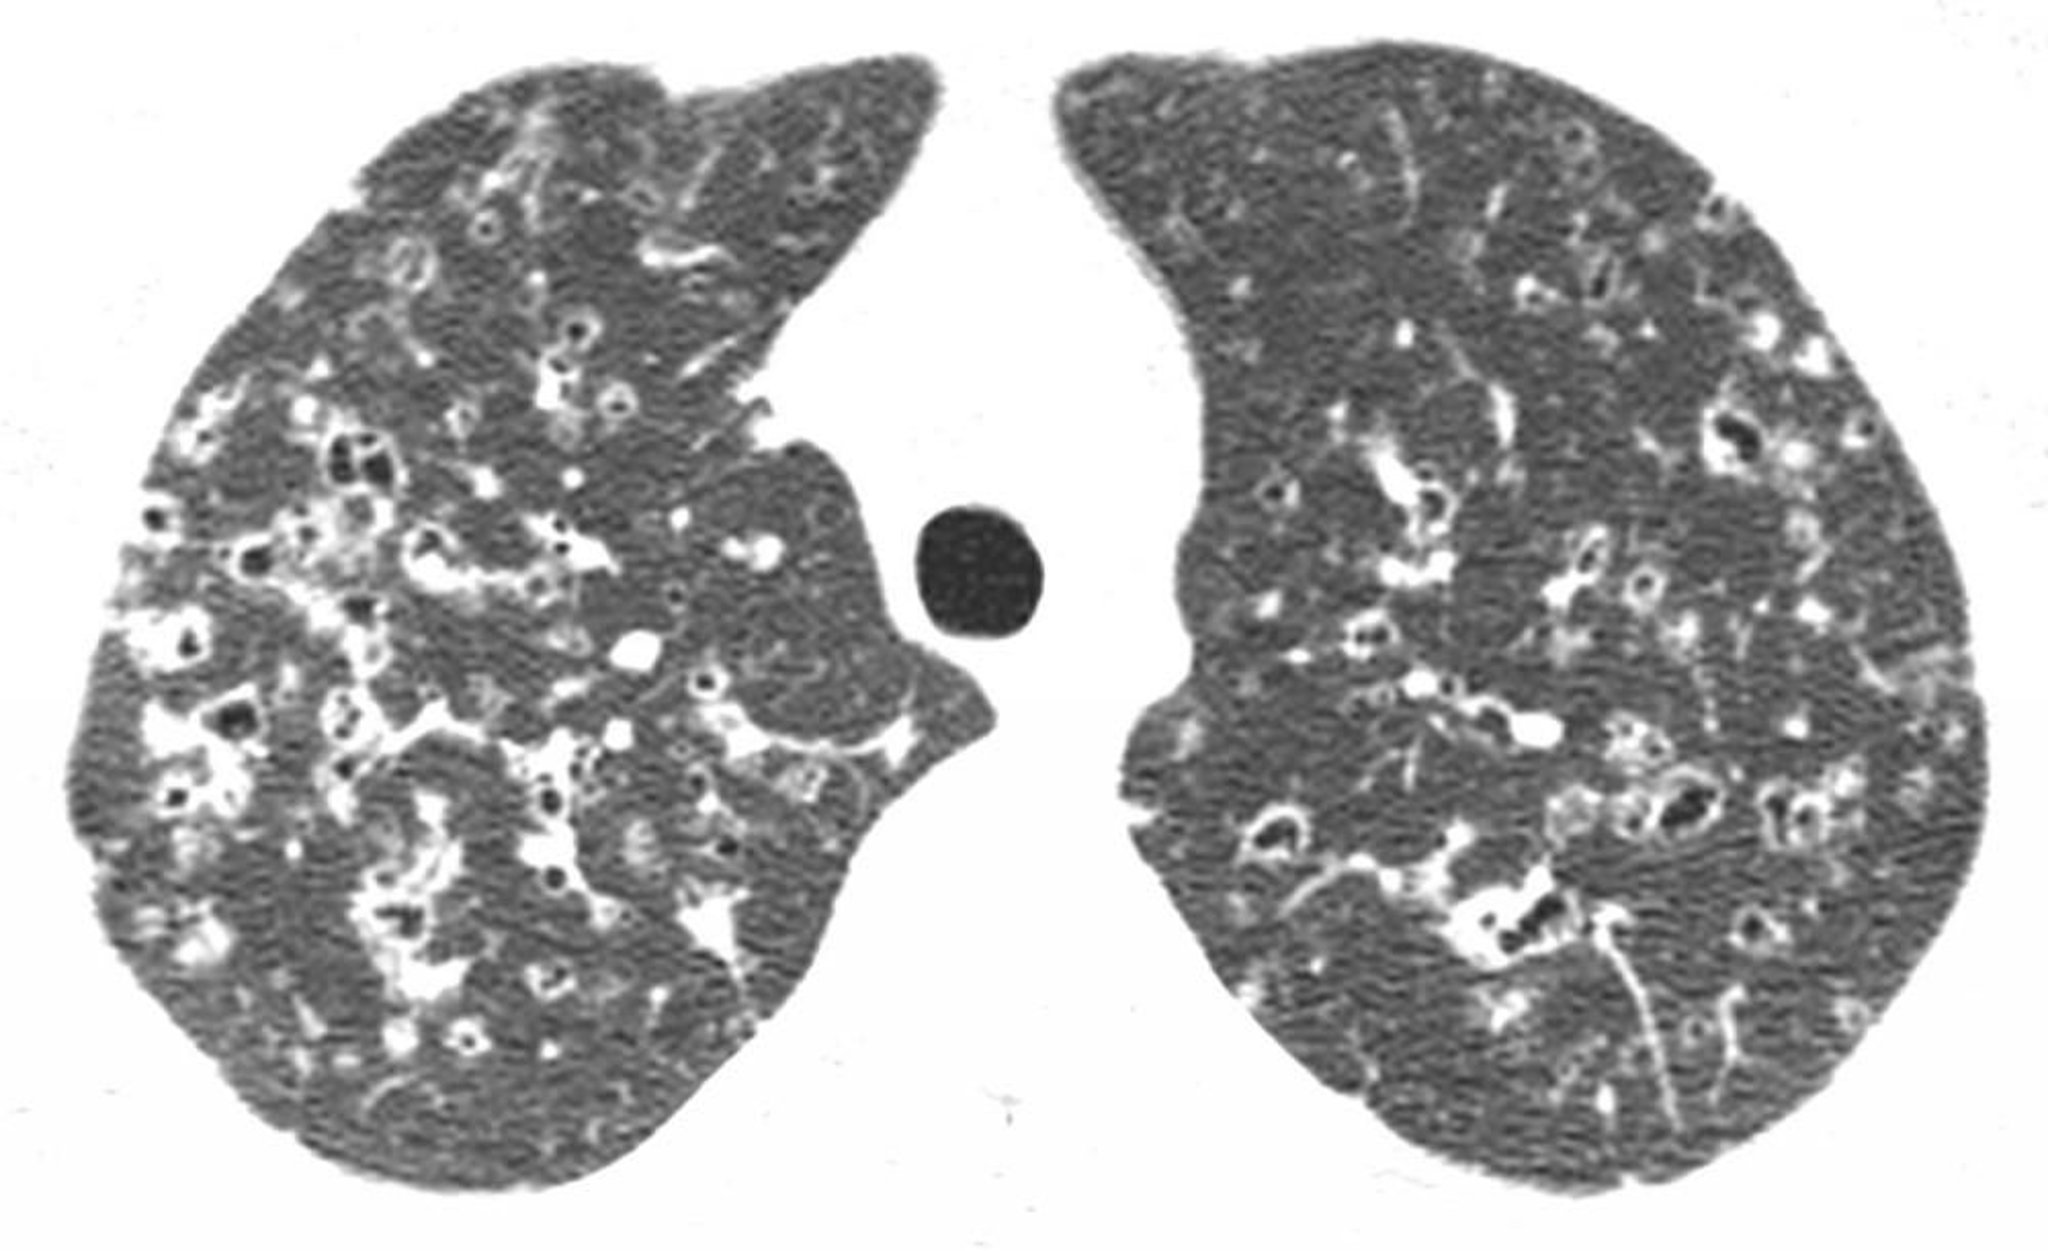

Pulmonale Langerhans-Zell-Histiozytose

Die hochauflösende CT durch die oberen Lappen zeigt Knötchen und unregelmäßige Luftdichte-Zysten, meist in der oberen und mittleren Lungenregion. Diese Befunde sind charakteristisch für eine Langerhans-Zell-Histiozytose bei einem Patienten mit Tabakkonsum in der Vorgeschichte.

Image courtesy of Harold R. Collard, MD.